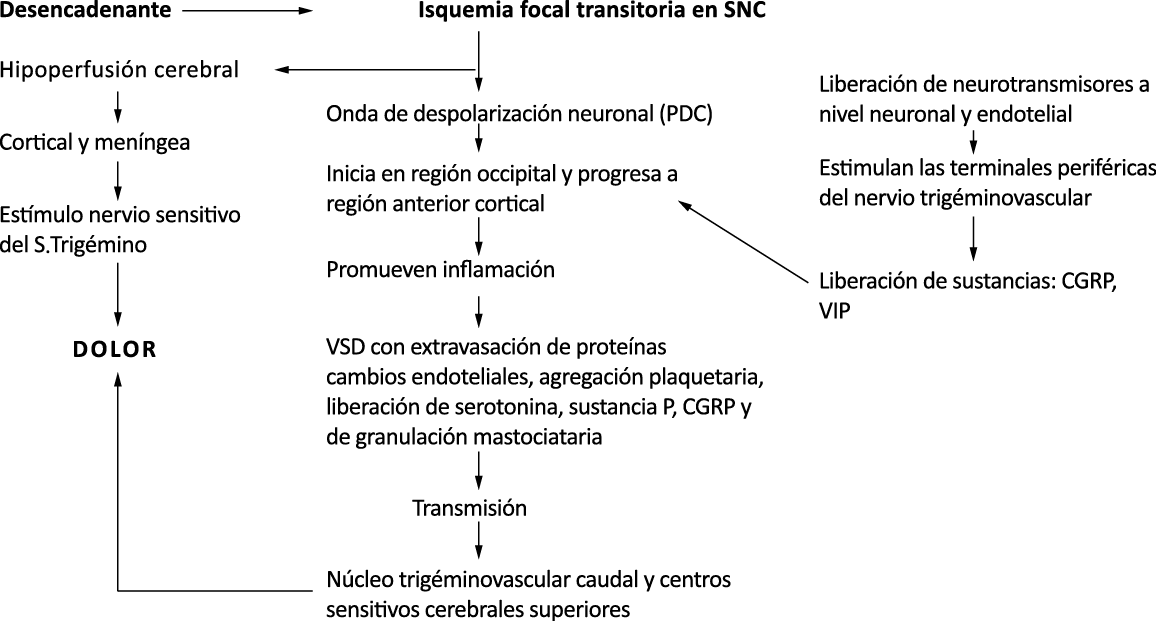

El aura de la migraña, al menos en su sentido clásico, tiene relación con la depresión cortical que se propaga por la corteza cerebral y participa como un actor paralelo cuando se producen las crisis. (Figura 2)

Se cree que una onda transitoria de despolarización neuronal de la corteza (Figura 9), la depresión de propagación cortical (CSD), es el mecanismo cerebral fisiopatológico subyacente al fenómeno clínico del aura de la migraña. Leão(21) estableció un mecanismo subyacente hipotético. Luego de haber estimulado eléctricamente la corteza de conejo y encontrar una depresión EEG que se propagaba a una velocidad similar de 3 mm/min centrífugamente desde el sitio de estimulación sugirió que podría ser la base del aura migrañosa. Esta hipótesis está fundamentada en la correlación entre las características neurofisiológicas de una CSD, su propagación retinotópica en la corteza visual y las características y dinámicas de los déficits visuales(14, 15) y en las observaciones indirectas derivadas de los estudios de imágenes que respaldan aún más este concepto(16) Sin embargo, sobre la base de la comprensión actual de la migraña, es poco probable que la CSD esté involucrada en el inicio del síndrome completo de la migraña(17).